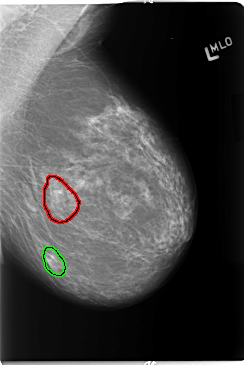

B_3110_1.RIGHT_MLO

FILE: B_3110_1.LEFT_MLO.OVERLAY

TOTAL_ABNORMALITIES 2

ABNORMALITY 1

LESION_TYPE CALCIFICATION TYPE PUNCTATE-PLEOMORPHIC DISTRIBUTION CLUSTERED

ASSESSMENT 4

SUBTLETY 3

PATHOLOGY BENIGN

TOTAL_OUTLINES 1

BOUNDARY

ABNORMALITY 2